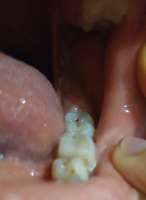

86AC4E2B-B68F-4[...].jpeg 1351Кб, 1919x1439

Такие дела. Зубу пиздец? В выходные пойду к стоматологу. Не болит, просто откололось и ЗИЯЕТ. За соседний зуб тоже страшновато

>>1240385

Аноним 18/08/21 Срд 00:25:00 124039795

Кариес на два зуба.